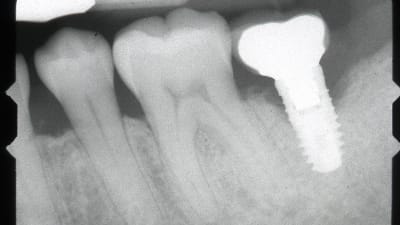

Case Reports Implantology Prosthodontics CAD/CAM Fabrication of Definitive Implant Prostheses: A Digital Workflow From Planning to Implant Placement to Final Restoration By Harold S. Baumgarten, DMD December 01, 2015 10 min read

Clinical Technique Review Implantology Salvaging Implants With an Nd:YAG Laser: A Novel Approach to a Growing Problem By Jon B. Suzuki, DDS December 01, 2015 13 min read